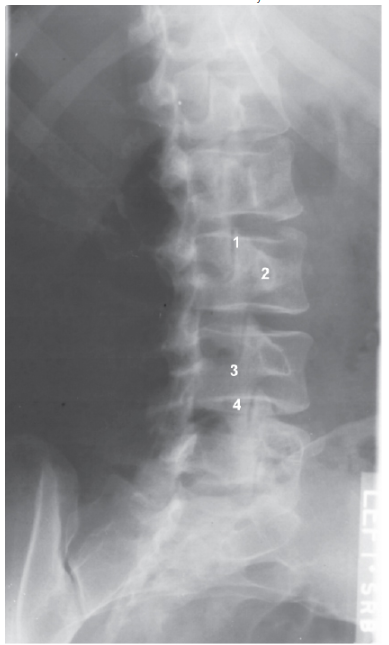

What is the anatomic structure indicated by number 1 in the radiograph shown below?

A - Superior articular process

An LPO projection of the lumbar spine is shown. The patient is positioned so that the lumbar spine forms a 45-degree angle with the IR. The zygapophyseal joints (those closest to the IR) are well demonstrated in this position. The typical “Scottie dog” image is depicted. The “ear” of the Scottie is the superior articular process (number 1), and the front foot is the inferior articular process (number 4). The Scottie’s eye is the pedicle, its body is the lamina (number 3), and its nose is the transverse process (number 2).

What is the anatomic structure indicated by number 4 in the radiograph below?

B - Inferior articular process

An LPO position of the lumbar spine is shown. The patient is positioned so that the lumbar spine forms a 45-degree angle with the IR. The zygapophyseal joints (those closest to the IR) are well demonstrated in this position. The typical “Scottie dog” image is depicted. The “ear” of the Scottie is the superior articular process (number 1), and the front foot is the inferior articular process (number 4). The Scottie’s eye is the pedicle (number 2), its body is the lamina (number 3), its nose is the transverse process (number 5), and its neck is the pars interarticularis (number 6).